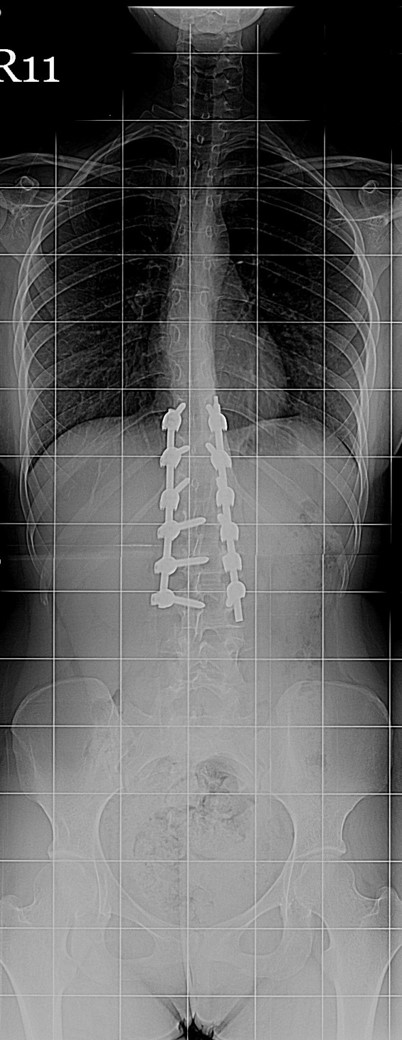

20 Yaşında Kadın Hasta

Boy: 171.3cm.

Kilo: 66kg

Rib hump lomber 10 derece

Ameliyat Öncesi

Ameliyat Sonrası